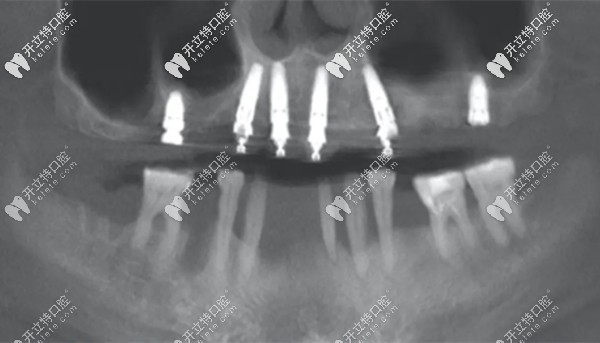

all-on-six即刻種植牙的全景片

(這就是all-on-six即刻種植后的全景片)

但,上/下頜各植入6顆牙根的全口種植牙,不是都叫all-on-6即刻種植牙哦~它也可以是以點(diǎn)種的方式來(lái)植入,就如下圖所示? ?↓

能看懂么?這張全景片中的上頜六顆種植體,就是“點(diǎn)種”技術(shù)。分別選取牙槽骨量較為充沛的部位,將牙根種入。

兩側(cè)后牙可以明顯看出,用的是較短的種植體,這樣的好處是可以避免植骨手術(shù)。